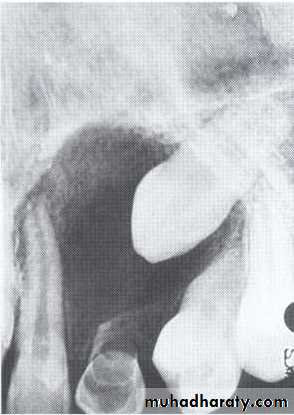

Benign cyst: lack of peripheral cortex(retention

pseudo cyst) indicates that it originated in the

sinus (non-odontogenic origin).